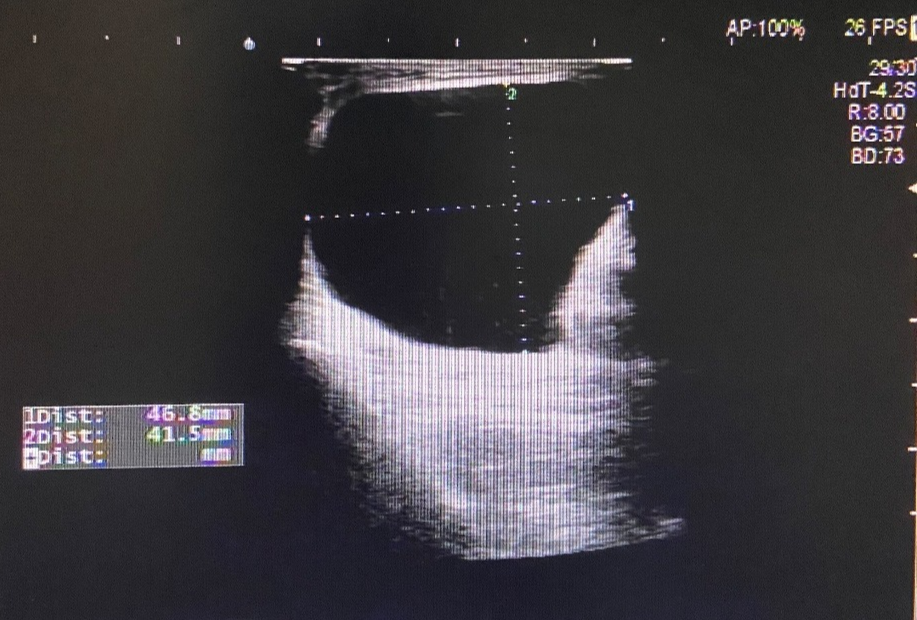

图片

图 1 左侧腹股沟区包块

超声所见

左侧腹股沟区见范围约 4.4cm×3.2cm×2.0cm 无回声区,可见少量分隔,增减腹压大小无明显变化。右侧腹股沟区未见明显异常回声。

超声提示

左侧腹股沟无回声区,子宫圆韧带囊肿?积液?

术后证实为左侧子宫圆韧带囊肿。